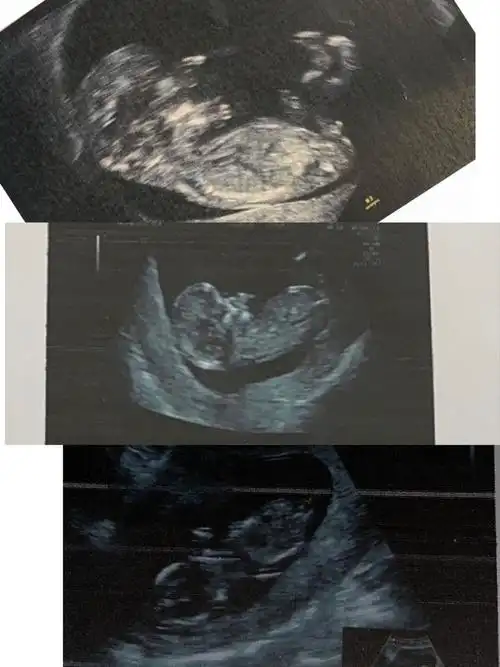

[试管婴儿]nt和13周拍的b超.大家帮忙看看nub点是男是女?